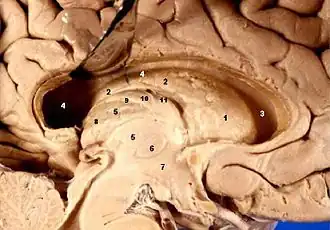

Location of the human hypothalamus

Location of the hypothalamus (cyan) in relation to the pituitary and to the rest of the brain